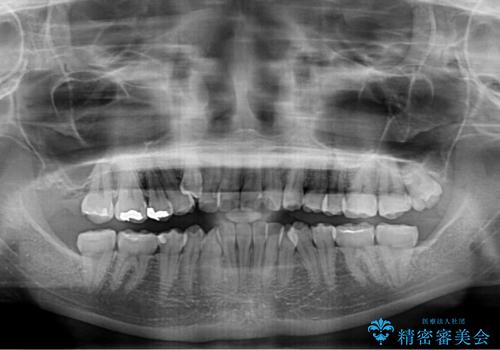

- 上下の八重歯と前歯のデコボコを気にして来院された患者様です。

右上と左下の八重歯が特に著しく、上顎正中が右側にシフトしていました。

デコボコが強いため小臼歯4本を抜歯し、上顎正中を左側に移動させるために補助装置を使用して、ワイヤー装置にて矯正治療を行うこととしました。